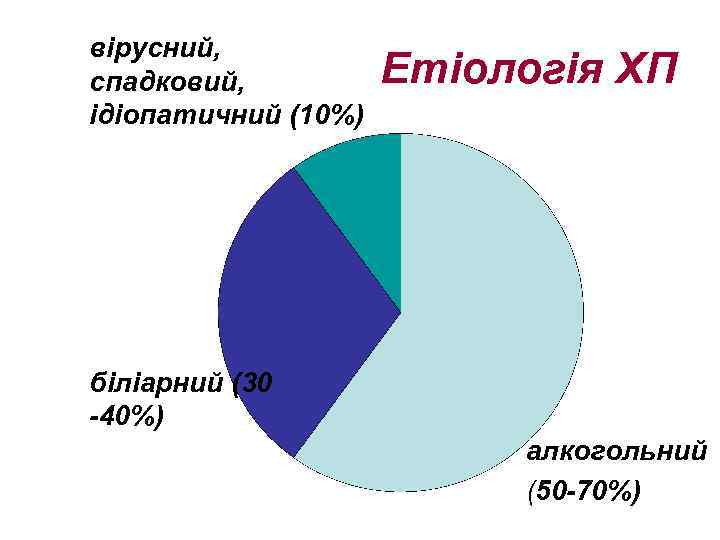

вірусний, спадковий, ідіопатичний (10%) Етіологія ХП біліарний (30 -40%) алкогольний (50 -70%)

вірусний, спадковий, ідіопатичний (10%) Етіологія ХП біліарний (30 -40%) алкогольний (50 -70%)